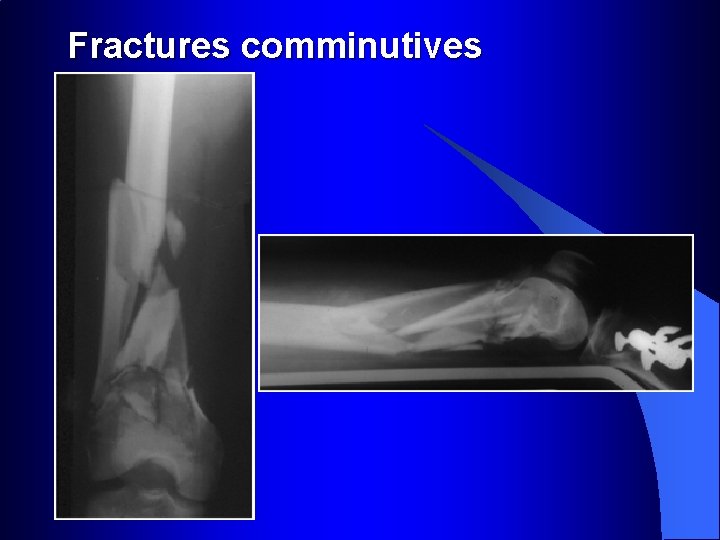

Fractures comminutives

Fractures comminutives : pontage par plaques